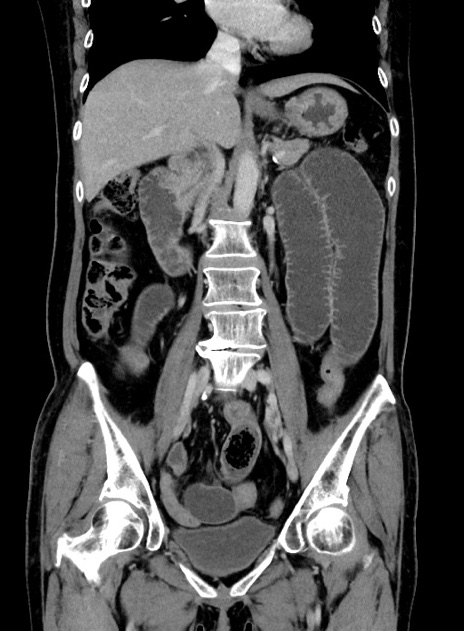

横断像

【症例】 60歳代女性

【主訴】むかつき、みぞおちの痛み

【現病歴】3日前よりむかつきがあり、食事がとれない。

【既往歴】糖尿病

【身体所見】発熱なし、心窩部圧痛軽度あるも、腹膜刺激症状なし。

【データ】WBC 7400、CRP 1.92